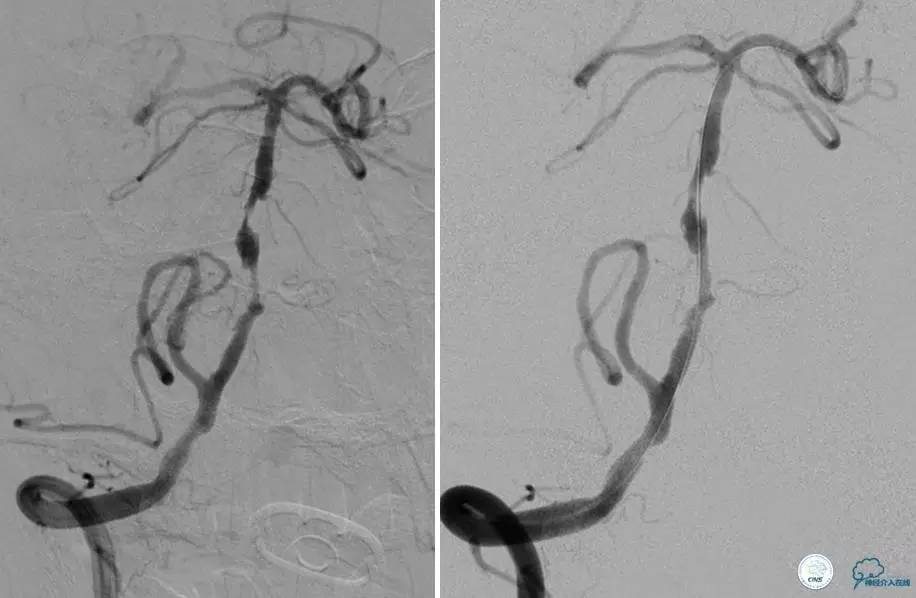

患者:49岁女性,脑梗死30天。

左侧颈内动脉末端闭塞,末端圆钝且有一定成角,开通难度较大,多次尝试导丝才成功穿过闭塞段。

开通效果很满意,术后症状明显恢复。

病例7

患者:反复发作右侧肢体无力、言语不清15天。

导丝很容易通过闭塞段。

顺利置入Wingspan支架,成功开通,手术顺利。